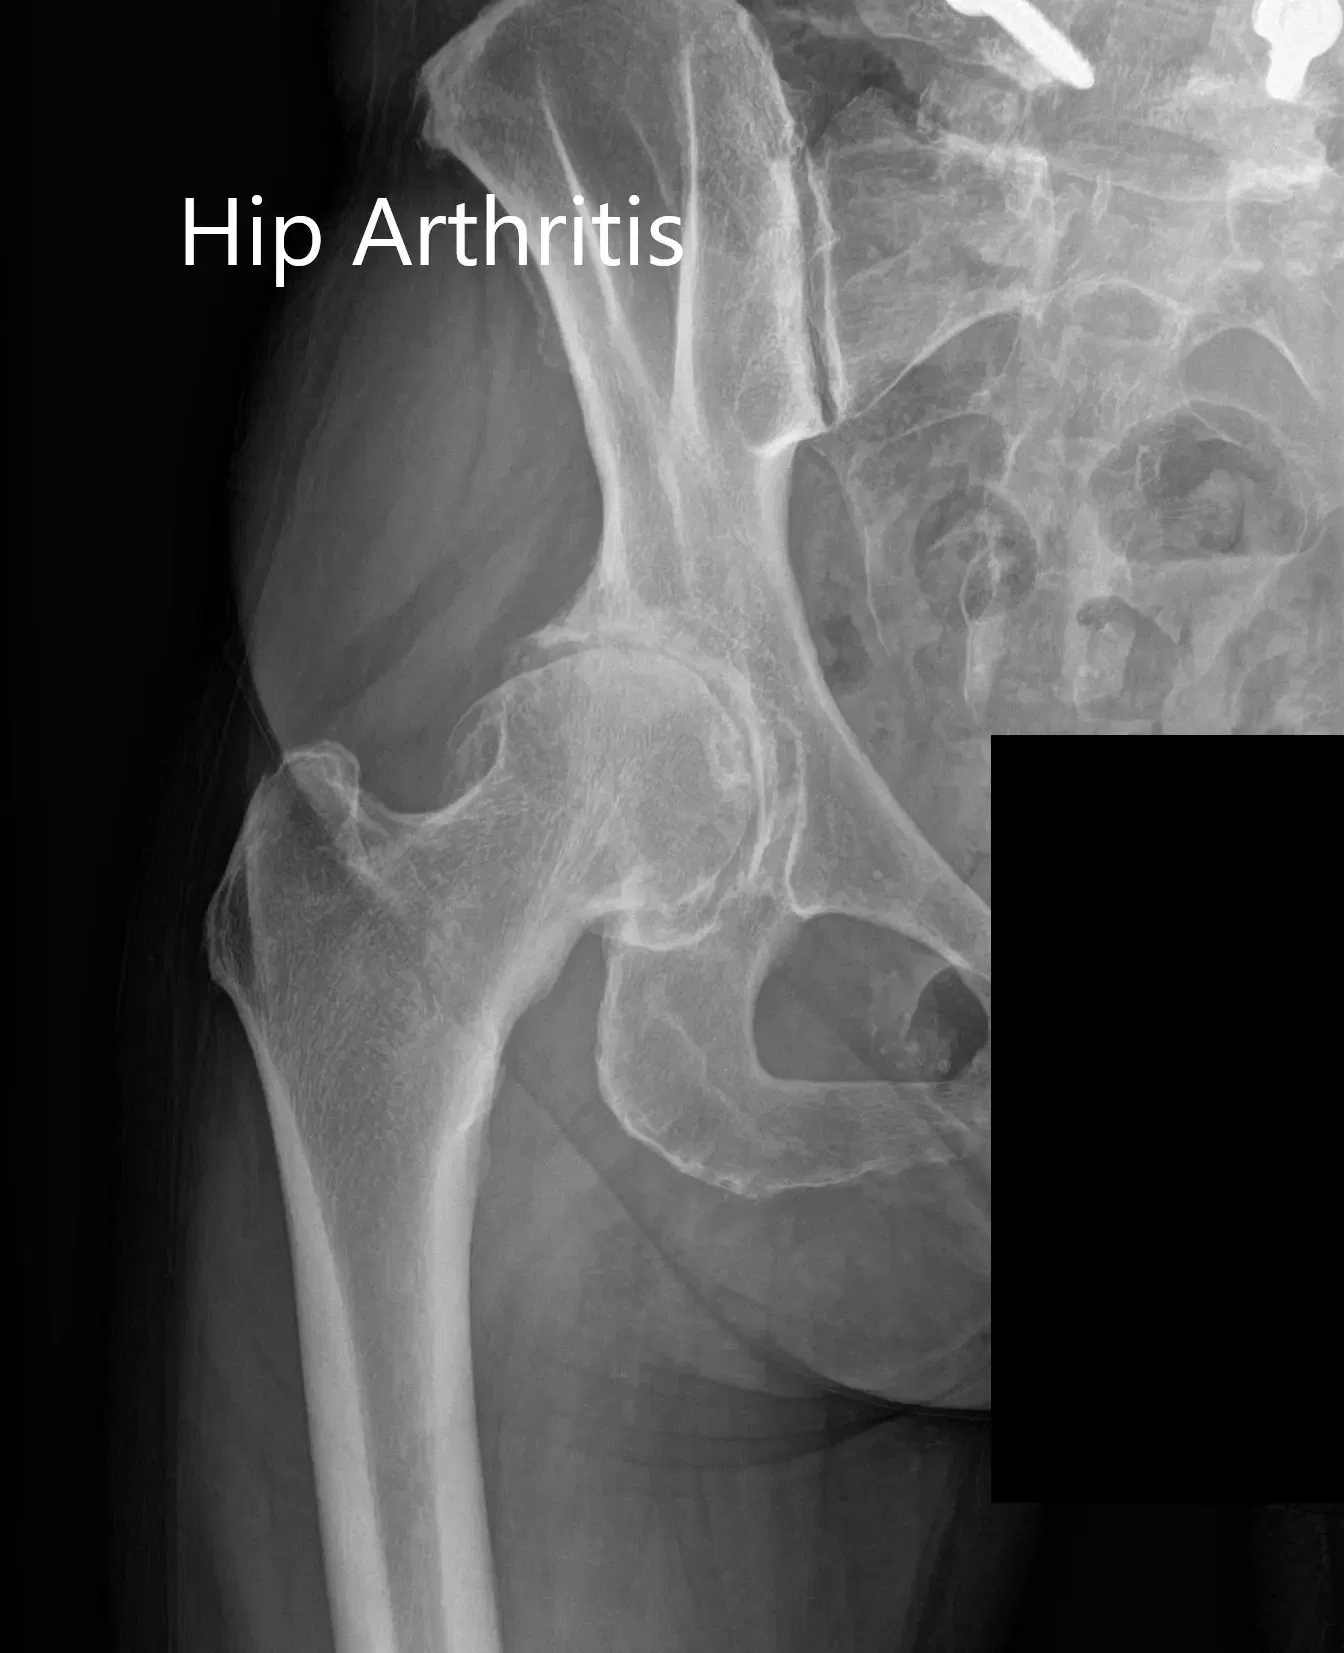

Las imágenes revelaron osteoartritis en la cadera derecha con reducción del espacio articular y osteófitos. Al paciente se le recomendó un reemplazo robótico total de cadera a la derecha. Los riesgos, beneficios y alternativas se discutieron extensamente con la paciente y ella estuvo de acuerdo con el plan.

Radiografía preoperatoria que muestra la vista de la parágrafe auricular y lateral de la cadera derecha.